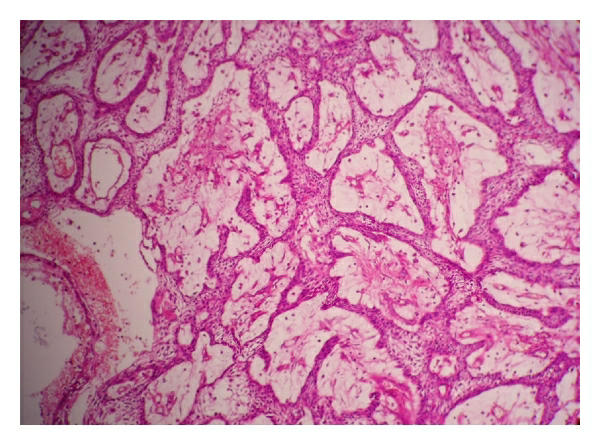

- Neoplastic odontogenic epithelium proliferates in long anastomosing strands or large sheets

- "Fishnet appearance"